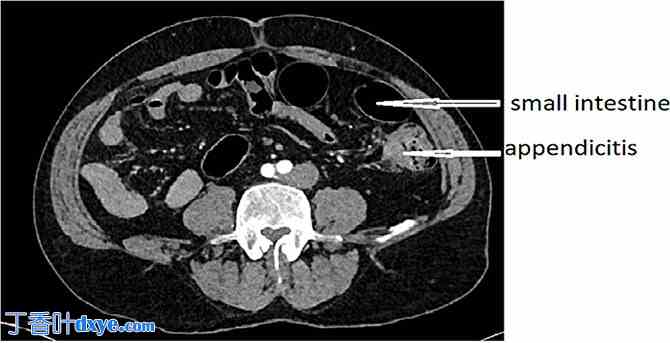

紧急 CT 扫描显示内脏反位(图 1),左侧高位阑尾炎(图 2)。

图 2。

左侧高位阑尾炎。